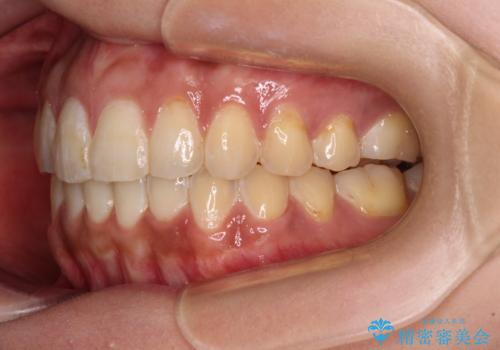

- 前歯のデコボコと上下前歯の隙間を気にして来院された患者様です。

下顎前歯はデコボコのため、歯肉が腫れやすくなっていました。

また、舌突出癖のため、上下前歯の間に隙間ができてしまい、上顎前歯が前方に傾斜している状態でした。

舌突出癖改善のためのトレーニングを行いながら、インビザラインにて矯正治療を行うこととしました。

舌のトレーニングをしっかりと行っていただき、上下前歯をしっかりと接触させることができました。

咬合力が強いため、治療途中に奥歯が咬み合わない期間が続きましたが、上下の奥歯でゴムかけを行っていただき、違和感なく咬み合うように仕上げることができました。